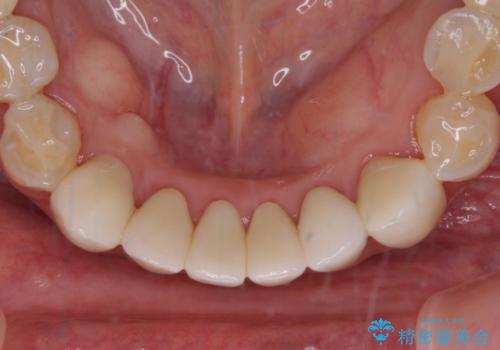

- 全顎的な歯肉からの出血と前歯の形態を気にして来院された患者様です。

診査の結果、上顎奥歯を中心に深い歯周ポケットが認められたため、歯周ポケット除去を目的とした歯周外科処置を行うこととしました。

歯周外科処置を行ったことで歯周ポケットはなくなり、毎回のブラッシングの度に嫌な思いをしていた出血は認められなくなりました。